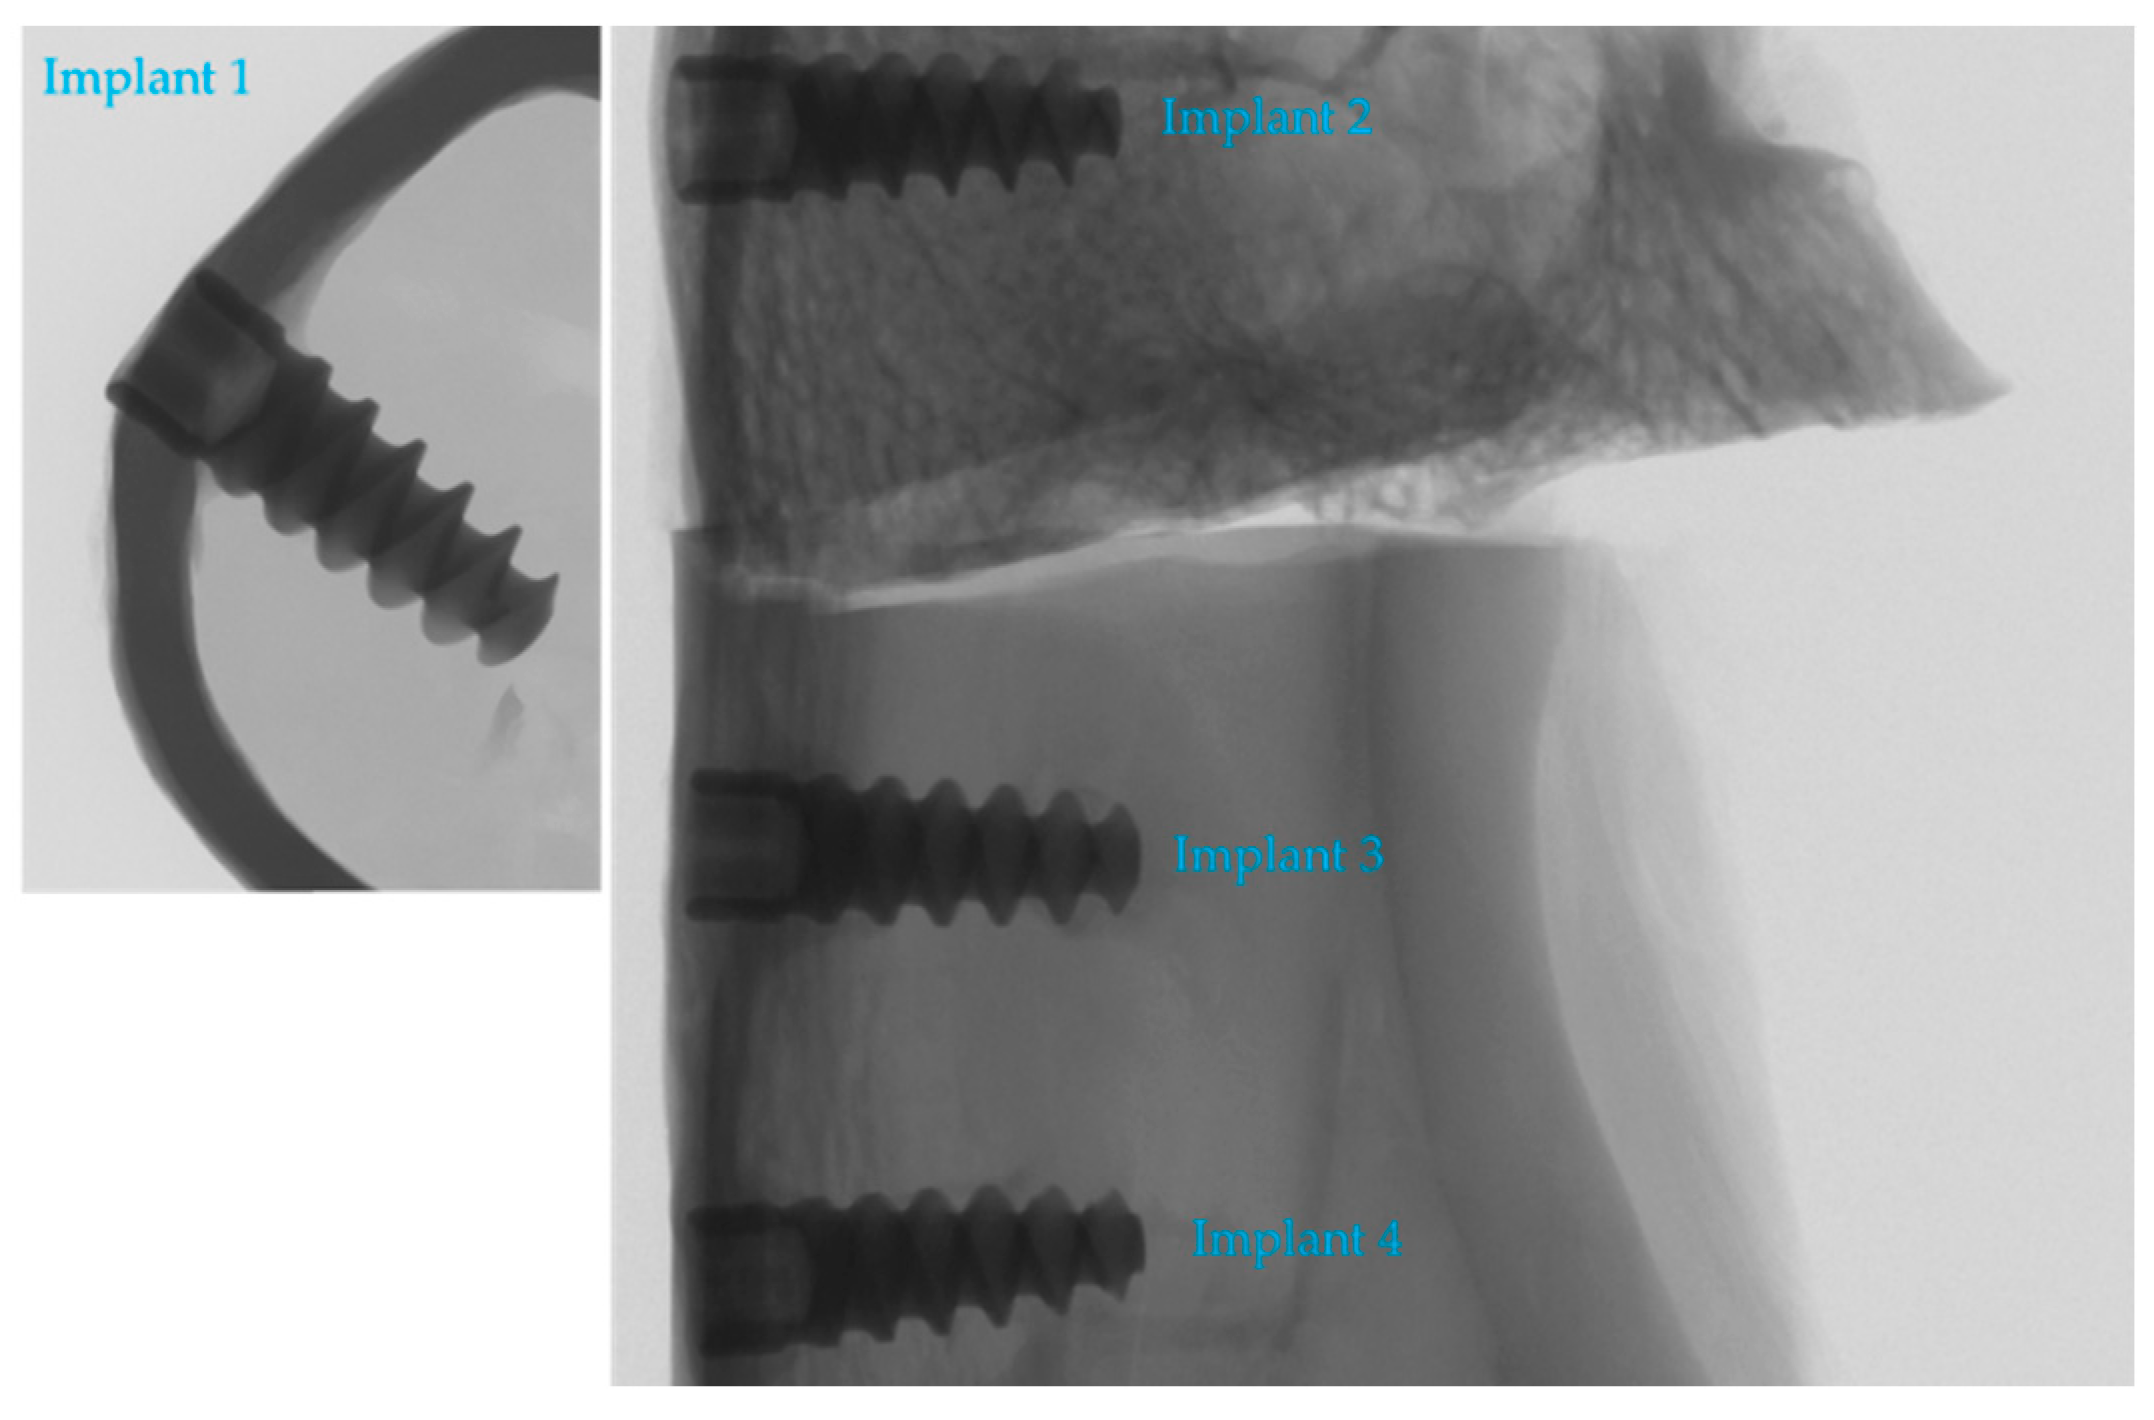

2.1. Implant Preparation

2.2. In Vivo Tests

2.4. Micro-Computed Tomography